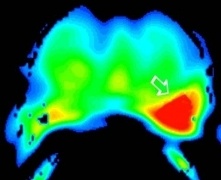

Dynamic contrast enhancement (DCE): is an MR technique that gives information on tumor angiogenesis (Figures 2a-2c).

Figure 2c: DCE images demonstrate a focal area of abnormal enhancement in the left mid gland (solid white arrow) corresponding to the region of tumor confirmed at prostatectomy.

prostate_mri_6

prostate_mri_8

prostate_mri_7

prostate_mri_9

Figure 4: Following the diagnostic MRI he underwent a MRI Guided prostate biopsy where only 2 cores were obtained through the left sided suspicious region in the prostate gland.